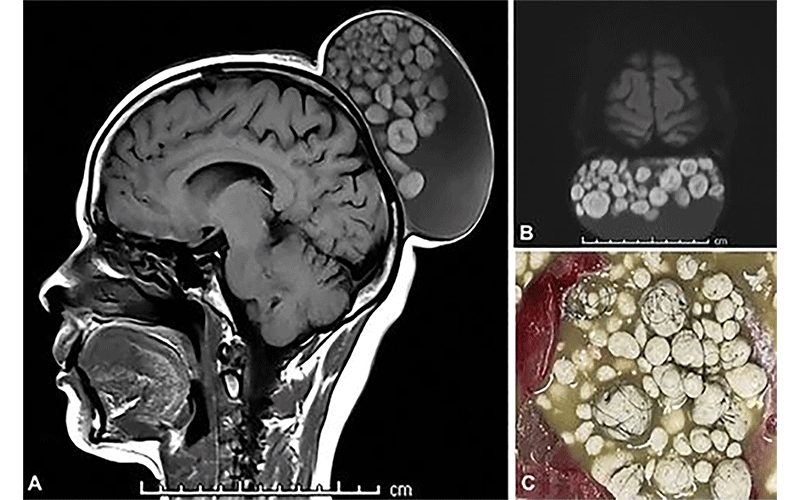

The 2023 Top Images in Radiology winner is entitled “Sack of Marbles Appearance of a Scalp Teratoma” by Sumit Thakar and Pavan Vasoya (1). The radiologicpathologic correlation of sebum-like material found in mature cystic teratomas, depicted on the MR and gross specimen images (Fig 1), is visually impressive, eye-opening, and educational. The illustration of this somewhat common entity in a less-common location embodies the core principles of radiology as a macropathology diagnostic specialty.

Images in a 52-year-old woman presenting with a scalp mass show a large cystic lesion in the subgaleal plane of the scalp with a “sack of marbles” appearance. (A) Sagittal unenhanced T1-weighted MRI scan shows a smooth-walled hypointense cyst with multiple spherical nodules that had isointense to hyperintense rims and thin hypointense cores. (B) Diffusion MRI scan shows the nodules demonstrating restricted diffusion. (C) Photograph of the gross specimen shows a sebumlike material within the cyst, hard spherical nodules, and strands of hair. https://doi.org/10.1148/radiol.230033 ©RSNA 2023